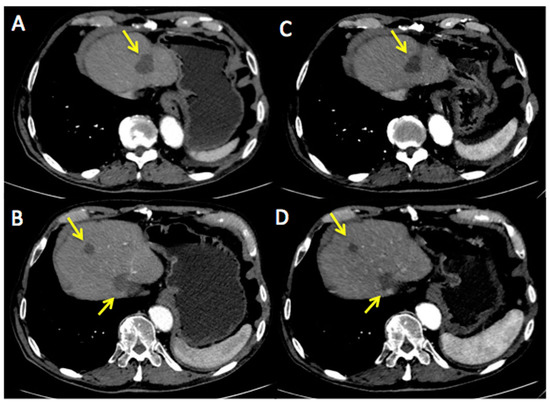

Figure 3 and Figure 4 represent two exemplar cases of patients judged to be PR and CR, respectively, at timepoint-2 evaluation.

Figure 3. A 55-year-old female affected by breast cancer with lung metastasis, subjected to 12 cycles of Bevacizumab-based chemotherapy and 24 hyperthermia sessions on the thorax, as first-line. Baseline Multidetector Contrast Enhancement Computed Tomography (MDCT) (A) showed metastasis in the superior right lobe of the lung (diameter: 17 mm × 12 mm, yellow arrow), confirmed by the increased 18F-Fluorodeossiglucose (18F-FDG) uptake on Positron Emission Tomography/CT (PET/CT) images in the same sites (green square, B). Timepoint-2 MDCT (C) evaluation demonstrated size decrease of lung metastasis (diameter 14 mm × 7 mm, yellow arrow) with 18F-FDG uptake decrease on PET/CT images (green square, D). According to mRECIST, patient was classified as PR. Ca15.3 and CEA values evaluated at baseline were 830 UI/mL and 135 ng/mL, respectively; while Ca15.3 and CEA values evaluated at timepoint-2 were 115 UI/mL and 40 ng/mL, respectively. Side effects reported were limited to asthenia and peripheral sensory neuropathy.